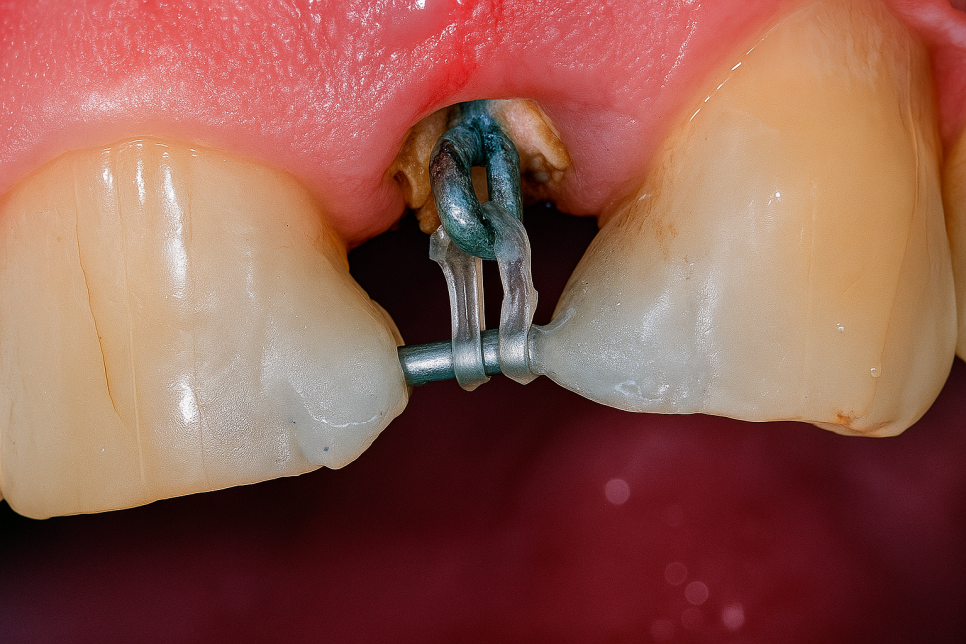

때문에 인위적으로 이를 끌어올려 주어야

진료가 가능한데 이것을 정출술이라 합니다.

교정으로 정출을 유도하는 것과,

✅ 교정

브라켓이나 철사 같은 교정 기구를

부착해 서서히 이를 움직이게 해서

잇몸 밖으로 당겨내는 방식을 말합니다.

이가 움직일 때마다 주변 치조골과

부착 치은도 따라 올라오기 때문에

뼈와 치은의 재생 및 재형성에도 유리합니다.

보통 근관치료와 동시에 이루어져

1~2달 정도 소요되는 편이며,

자연스러운 이동 방식이기 때문에

주위 조직 손상이 적다는 강점을

갖고 있습니다.